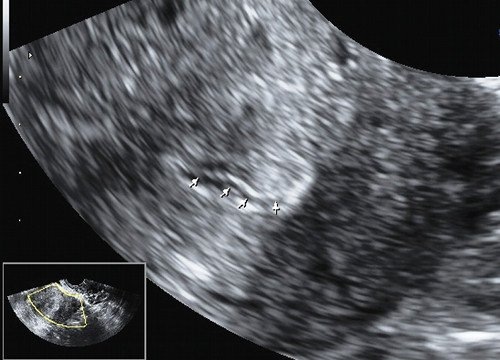

Во время осмотра на кресле, доктора заметила образование в цервикальном канале, которое кровоточило при контакте. На УЗИ цервикальный канал был расширен до 4-5 мм, визуализировалось гиперэхогенное образование на ножке, размером 13х7 мм, исходящее из стенки канала и перекрывающее его просвет примерно на 70%.

На основании анамнеза, данных гинекологического осмотра (визуализация образования в области наружного зева) и УЗИ (образование в цервикальном канале, перекрывающее его просвет) установлен диагноз: полип цервикального канала.